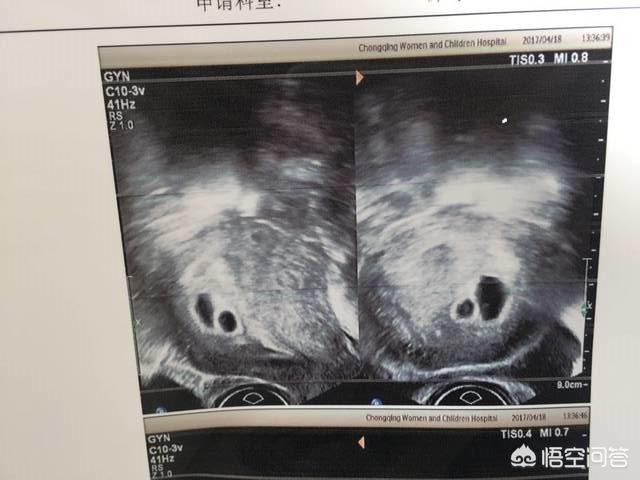

“双胞胎”胎儿是怎么形成的?双胞胎的形成通常分为2大类,即单卵双胎和双卵双胎,这两大类中的双胞胎又有四种不同的形成方式:

一、双卵双胎

通常情况下女性每个月只排出一个卵子,极偶然时有一个月排出两个卵子或者三个卵子的情况出现。当排出两个卵子时,恰逢有大量精子来访,出现两个精子分别与两个卵子结合,就会形成双卵双胎。

单卵双胎是由一个授精卵分裂而成。大家可以通俗的理解成一个受精卵多复制了一份。这样的双胎性别相同,遗传特征相同。单卵双胎又分为三种形成方式:

1、卵裂期分离,分别发育成两个卵泡。有个自的绒毛膜、羊膜和胎盘。

2、卵泡期内细胞群分离,形成两个胚盘,但胎盘是一个(请注意胚盘和胎盘不同!)。两个胎儿虽然共同生活中在同一个绒毛膜内,但有各自的羊膜腔。

3、胚盘期形成两个原条,各自发育成胎儿。两个胎儿共用同一个绒毛膜、羊膜腔和胎盘。